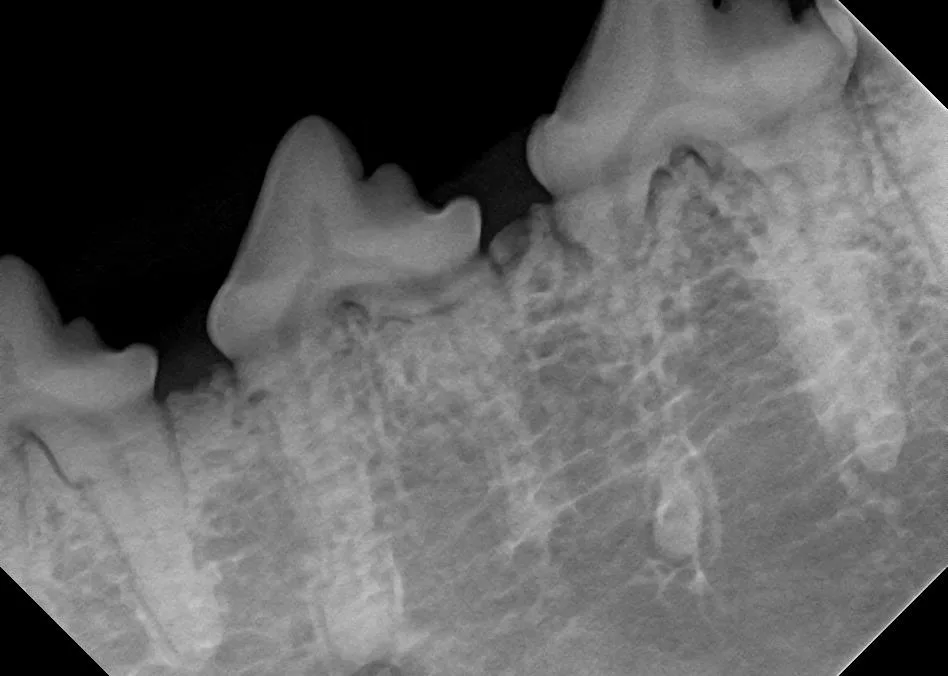

Iatrogenic fracture of the jaw can be a serious complication of surgical extractions and is most commonly associated with surgical extraction of mandibular canine teeth in dogs and cats and mandibular first molar teeth in dogs (Figure 10). These extractions can be difficult to perform, as the root apexes are often located in close proximity to the ventral cortex of the mandible, possibly leading to significant bone loss when severe disease is present and increasing the risk for iatrogenic fracture (Figure 11).

Severe periodontal disease affecting the right mandibular first molar tooth in a dog. Careful extraction technique is necessary to extract the tooth without creating an iatrogenic fracture.

Preoperative intraoral radiographs are critical for assessing fracture risk, especially prior to surgical tooth extraction, and can be used to modify the procedure or refer a patient with high fracture risk to a board-certified veterinary dentist.